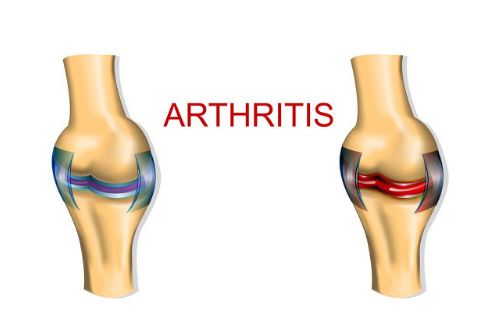

缺硒导致骨关节炎发病

骨关节炎是一种退行性骨关节病,年龄、关节变形及肥胖均是该病的危险因素。实验研究证明,关节炎患者滑膜组织中硒含量减少,体内抗氧化能力减弱,软骨细胞膜受到破坏,自由基引起软骨细胞的凋亡,引起关节软骨萎缩变薄,产生关节退变。生理浓度的硒可提高机体细胞和体液免疫功能。从以上不难看出,食用富硒食品对于骨关节炎的防治是有帮助的。